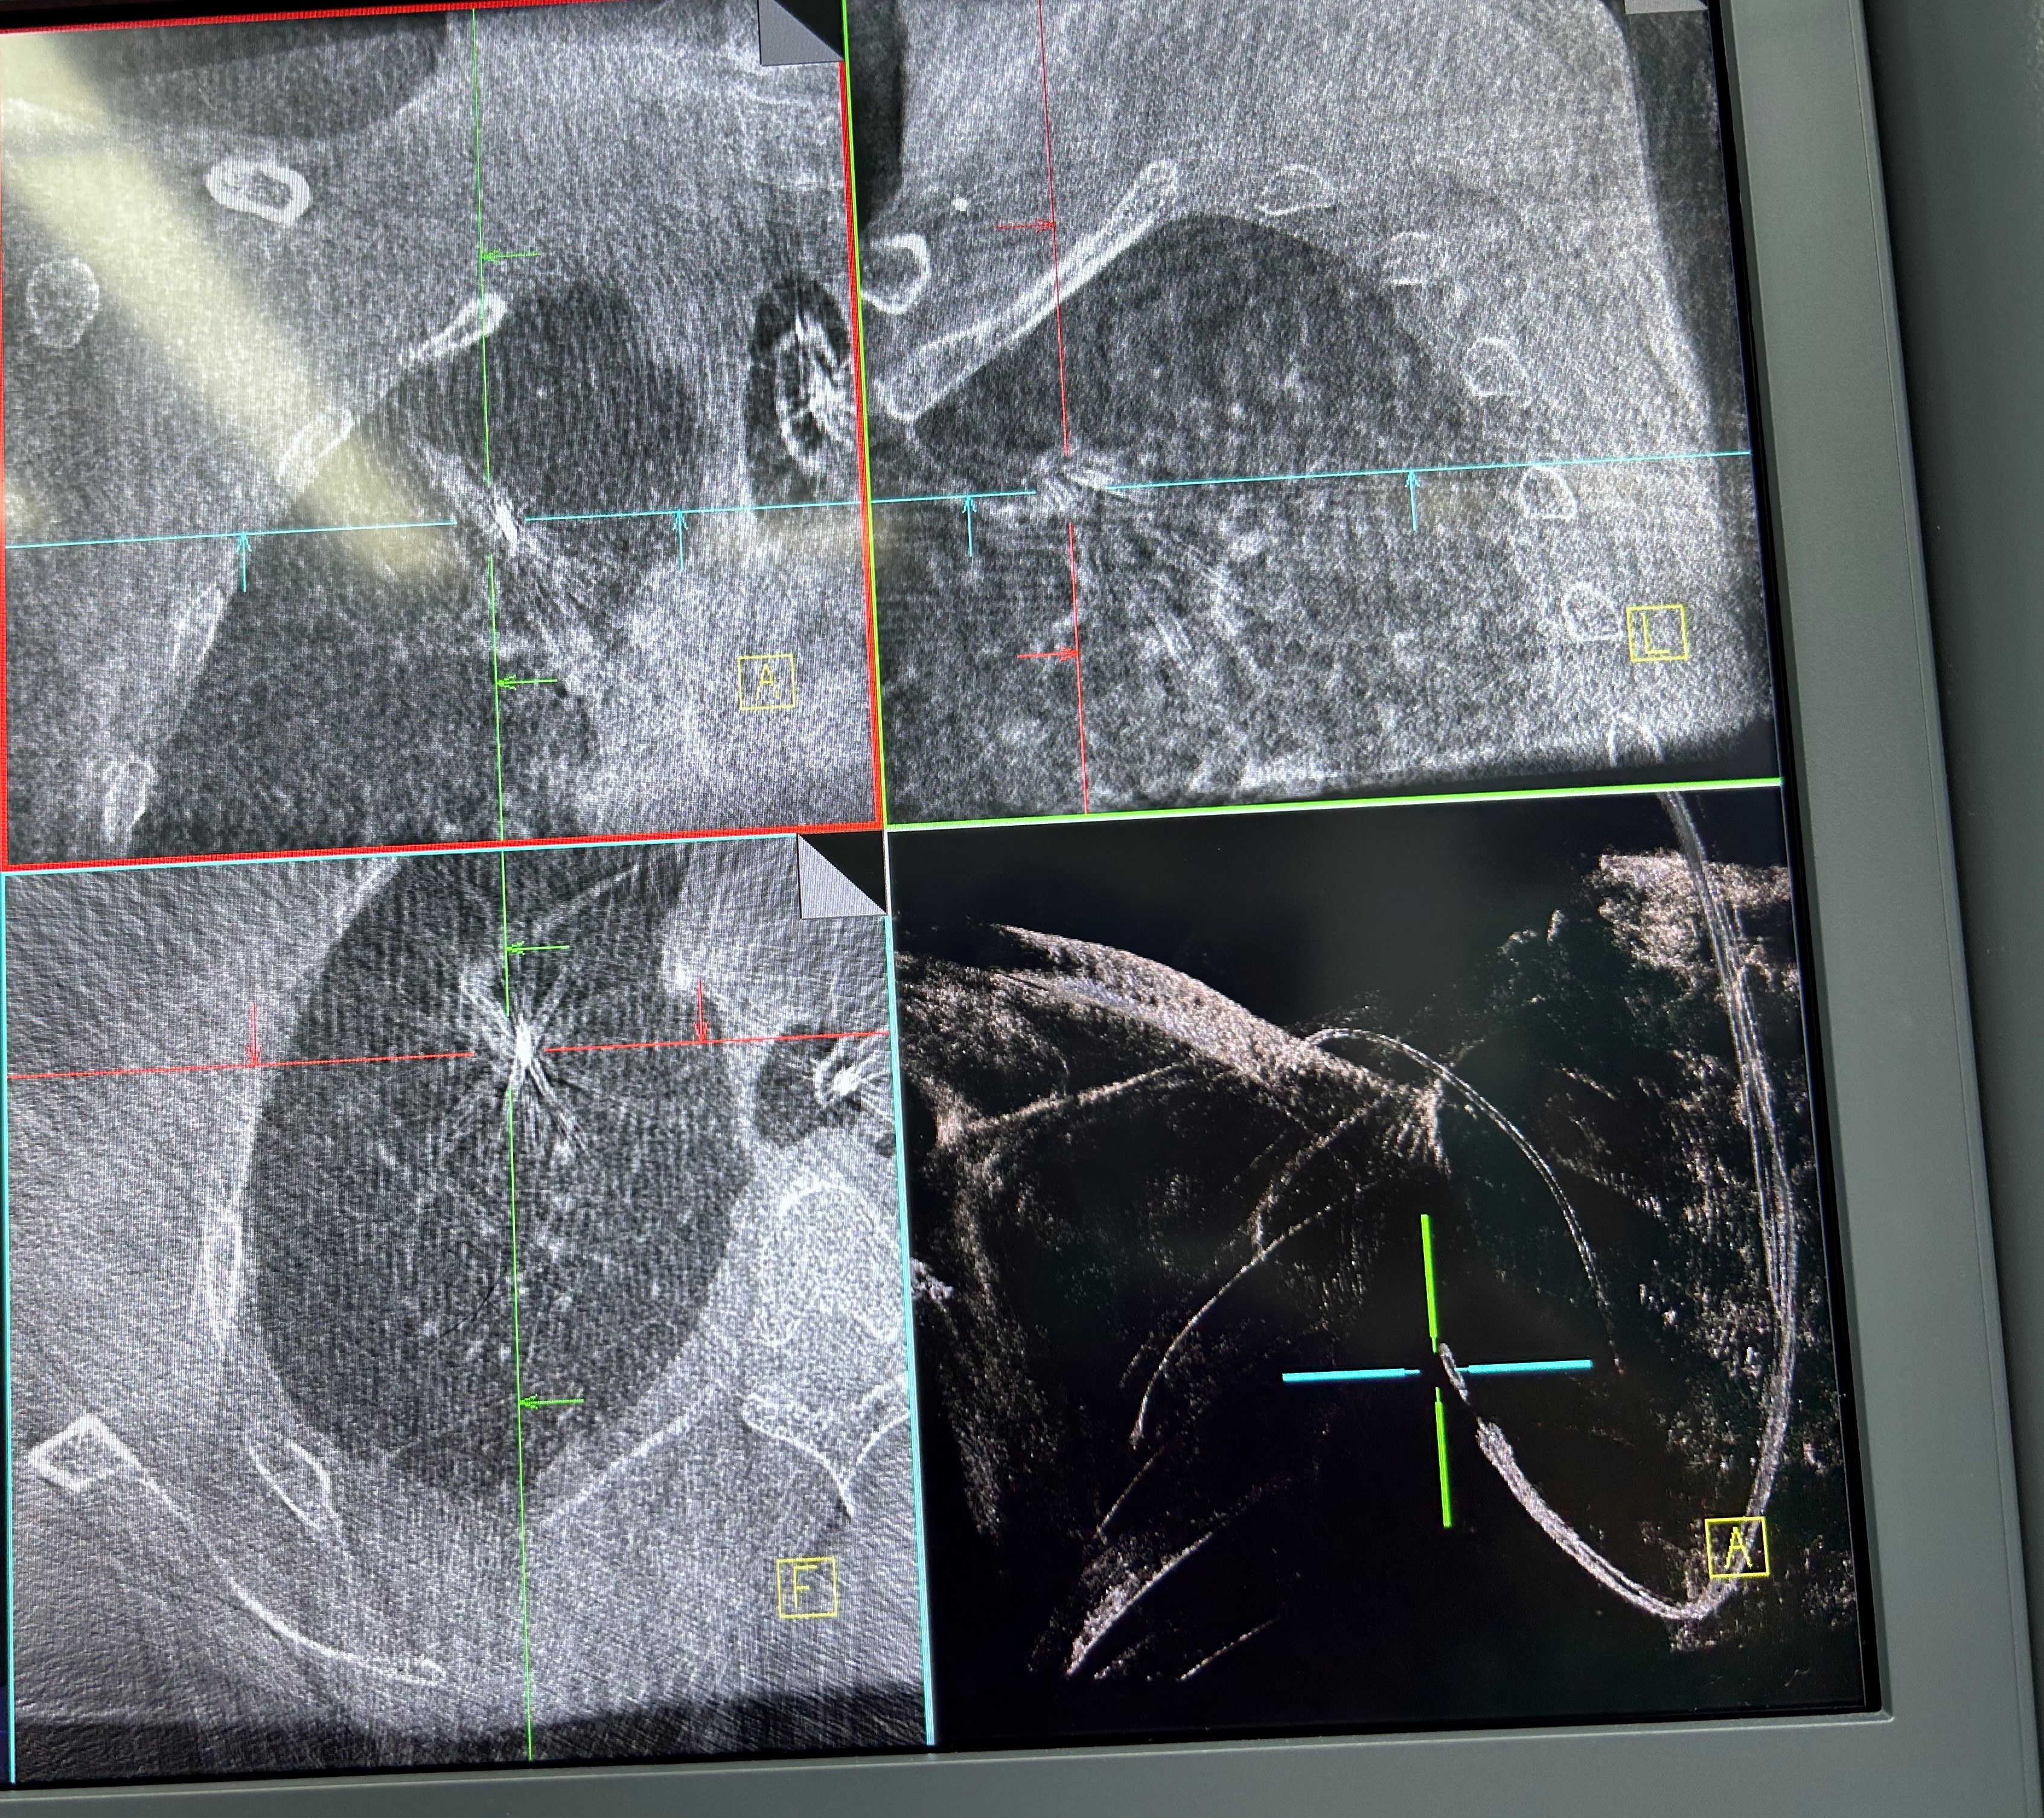

手术当日,呼吸科团队帮助患者在全麻下完成气管插管,手术由蒋军红主任指导,负责手术方案的实时优化与安全保障。曾大雄主任医师和王兰主任医师精准操作机器人支气管镜,在支气管镜导航机器人的精准引导下,通过AI三维重建、智能路径规划以及多模态信息融合,将支气管镜精准“引导”至右上叶尖段病灶处。随后,团队启动CBCT(锥形束计算机断层扫描)通过实时影像复核确认靶病灶,实现病灶“毫米级”精准锁定,彻底解决肺部病灶“找不到、找不准”的核心难题。机器人气管镜导航技术实现了从术前规划到术中操作全流程的智能精准控制,真正做到了肺部病灶的精准覆盖。

明确肿瘤诊断后,治疗方案即刻启动。团队经导航引导鞘管,精准插入一次性冷冻消融针(直径仅1.9mm)。再次通过CBCT确认消融针完全“扎根”于右上叶尖段病灶内后,开启冷冻治疗模式:以-160℃深低温冷冻10分钟、复温至45℃维持3分钟为一个治疗循环。完成了3次循环后,为确保病灶无遗漏,团队微调消融针位置,再次追加2次循环治疗。术后复查CBCT显示,病灶已呈现典型的冷冻后改变,术后两天复查胸部CT提示消融范围满意,治疗效果完全达到预期。整个手术过程中,患者生命体征始终平稳,术后第二天即可下床活动,真正实现了“微创治疗、快速恢复”的目标。